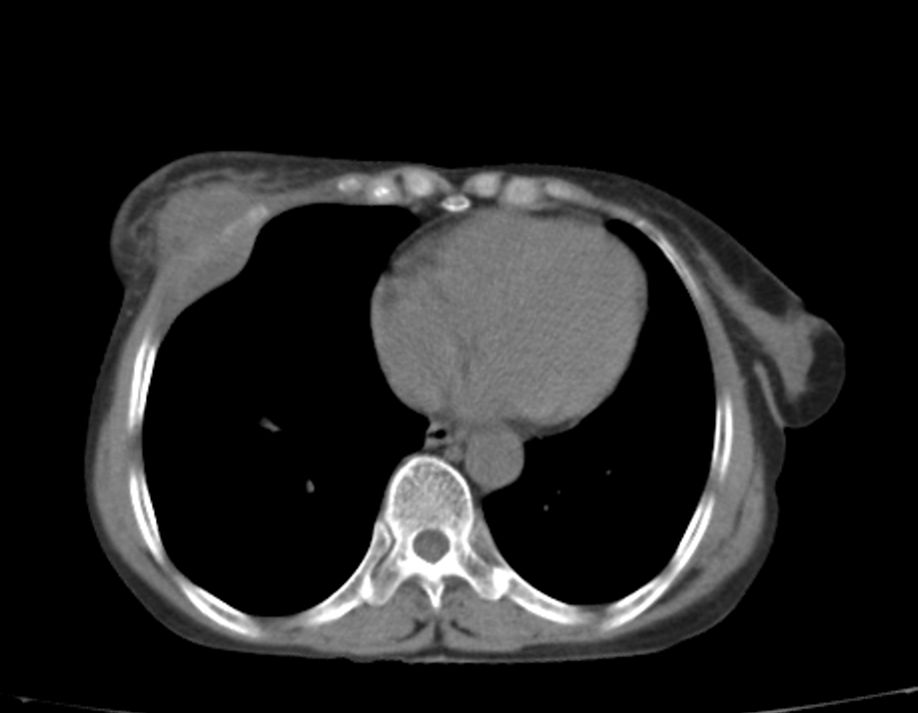

标题: CT21609:右乳包块1年,请各位讨论分析一下,乳腺CA, [打印本页]

标题: CT21609:右乳包块1年,请各位讨论分析一下,乳腺CA,

考虑---右乳癌并胸壁、肋骨、双肺转移。

考虑乳腺癌侵犯肋骨、胸壁及两肺转移可能性大。

右乳癌并胸壁、肋骨、双肺转移。

考虑右侧乳腺癌侵犯肋骨、胸壁及两肺转移。

支持考虑---右乳癌并胸壁、肋骨、双肺转移。

考虑右侧乳腺癌侵犯肋骨、胸壁及两肺转移可能。

考虑右侧乳癌并胸壁、肋骨及双肺多发性转移。